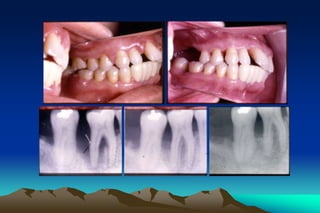

Limitation of the effectiveness of scaling and

root planing

1. Anatomy of roots

2. Depth of pockets

3. Areas of mouth being treatment

4. Inadequate instruments for diagnosis

5. Inadequate instruments for treatment

6. Range of mouth opening

7. Dexterity of operator

Limitation of theeffectiveness of scaling and root planing 1. Anatomy of roots 2. Depth of pockets 3. Areas of mouth being treatment 4. Inadequate instruments for diagnosis 5. Inadequate instruments for treatment 6. Range of mouth opening 7. Dexterity of operator